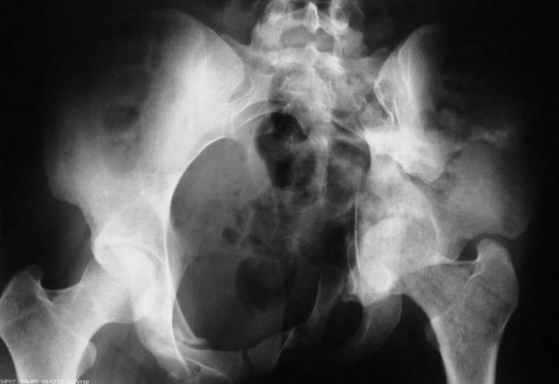

Рентгенограмма до операции